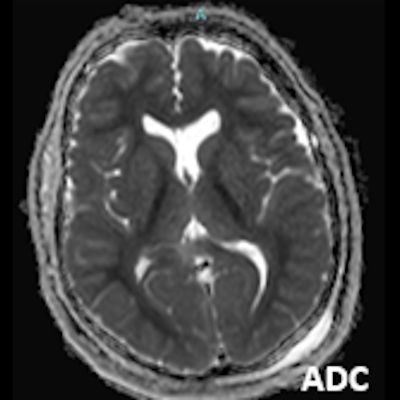

- A) Bilateral serebral kortekste (oklar) ve bazal ganglionlarda (oklar) yaygın DAG hiperintens, ADC hipointens difüzyon kısıtlamaları görülüyor.

- B) 9 gün sonraki difüzyon MR incelemede kortikal ve bazal ganglionlardaki difüzyon kısıtlamalarının gerilediği, bilateral serebral beyaz cevherde (oklar) ve internal kapsül arka bacağı- kortikospinal trakt boyunca (oklar) yaygın DAG hiperintens, ADC hipointens difüzyon kısıtlamalarının geliştiği izleniyor.

- T2A / FLAIR serilerde beyaz cevherde özellikle sentrum semiovalede diffüz yüksek sinyal görülür. Subkortikal U lifleri sıklıkla korunur.

- DAG görüntülemede sıklıkla belirgin difüzyon kısıtlaması görülür.

- Etkilenen beyaz cevher T1A görüntülerde sıklıkla hipointens olup kontrast madde verilmesi sonrası kontrastlanma görülmez. MR spektroskopide kolin ve laktat piklerinde artış ,NAA pikinde azalma görülür.